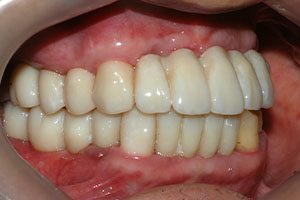

치료증례 전후사진

Before & After